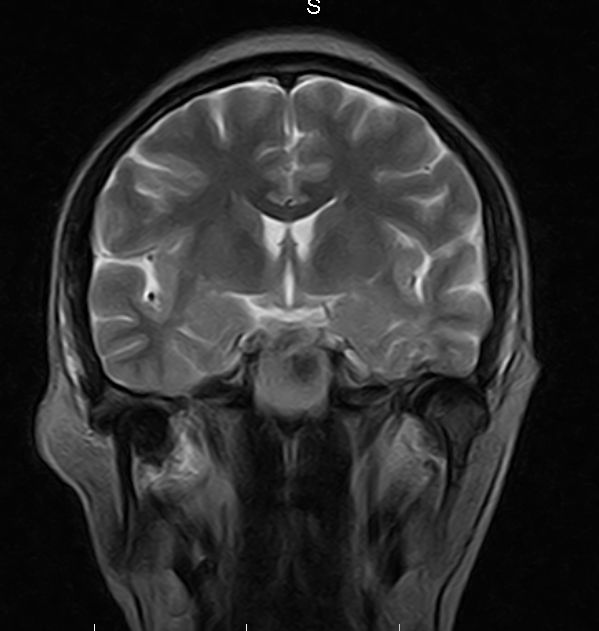

标题: MRI2379:30岁,男,癫痫10年,请各位看一下;CT示:左颞叶钙 [打印本页]

标题: MRI2379:30岁,男,癫痫10年,请各位看一下;CT示:左颞叶钙

考虑左侧颞叶脑血管畸形(avm)。----t1低等高混杂信号,t2等高信号周边较多流空血管影[冠状位明显],mra左侧大脑中动脉受压,远侧聚集.

海绵状血管瘤

支持海绵状血管瘤!